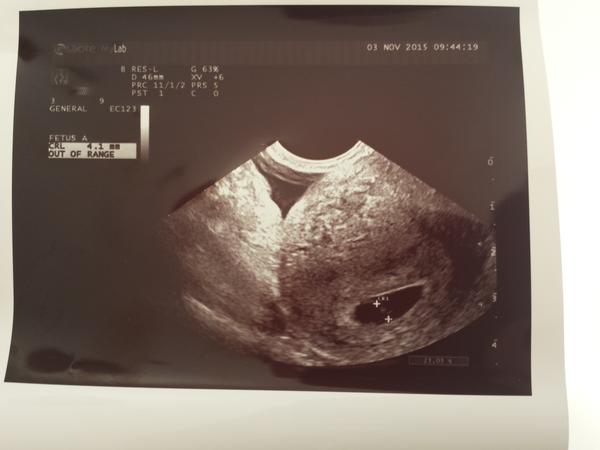

Ahojte bambuliacky moje takze u doktorky vsetko v naaaaajlepsom poriadku 🙂 Babenko ma 4,1mm je pekne zavrtane v maternici a sediecko na obrazovke blikalo ako o zivot 🙂 Vobec som necakala ze uz bude srdiecko 🙂 Dalsia kontrola-prva poradna o mesiac 🙂

Nech sa paci bambule tu je aj fotecka k nahliadnutiu 🙂 aj ked vela toho neuvidite cez foto, nazivo je to lepsie vidno 🙂 Takze predstavujem vam moju malu bublinku 😵